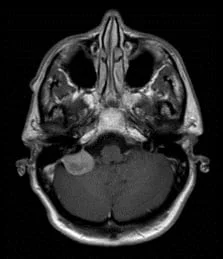

Un méningiome peut être diagnostiqué au scanner où il apparaît comme une masse ronde à la périphérie du cerveau, avec un épaississement de l’os au niveau de sa base d’insertion sur la méninge.

Il est plus fréquemment retrouvé sur une IRM sous forme d’une masse “blanche” après injection du produit de contraste intraveineux et entourée d’un œdème. Les méningiomes peuvent se rencontrer dans différentes localisations intra-crâniennes, plus ou moins facilement accessibles et qui conditionneront la technicité et les risques du geste qui vous sera proposé par votre chirurgien.